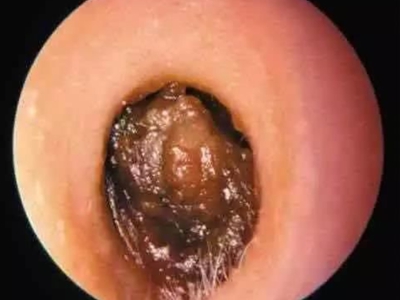

外耳道耵聍栓塞耳内完全堵塞图

外耳道耵聍栓塞患者外耳道分泌物干燥后形成碎屑或薄片,大量堆积后在鼓膜前方形成多层硬结,随着时间延长,颜色逐渐加深,呈褐色或红褐色。